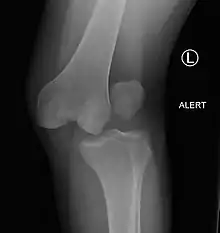

| Plain lateral X-ray of the left knee showing a posterior knee dislocation[1] | |

Plain X-rays, CT scan, ultrasonography, or MRI may help with the diagnosis.[2][11] Findings on X-ray that may be useful among those who have already reduced include a variable joint space, subluxation of the joint, or a Segond fracture.[5]

They may be divided into five types: anterior, posterior, lateral, medial, and rotatory.[4] This classification is based on the movement of the tibia with respect to the femur.[11] Anterior dislocations, followed by posterior, are the most common.[2] They may also be classified on the basis of which ligaments are injured.[2]